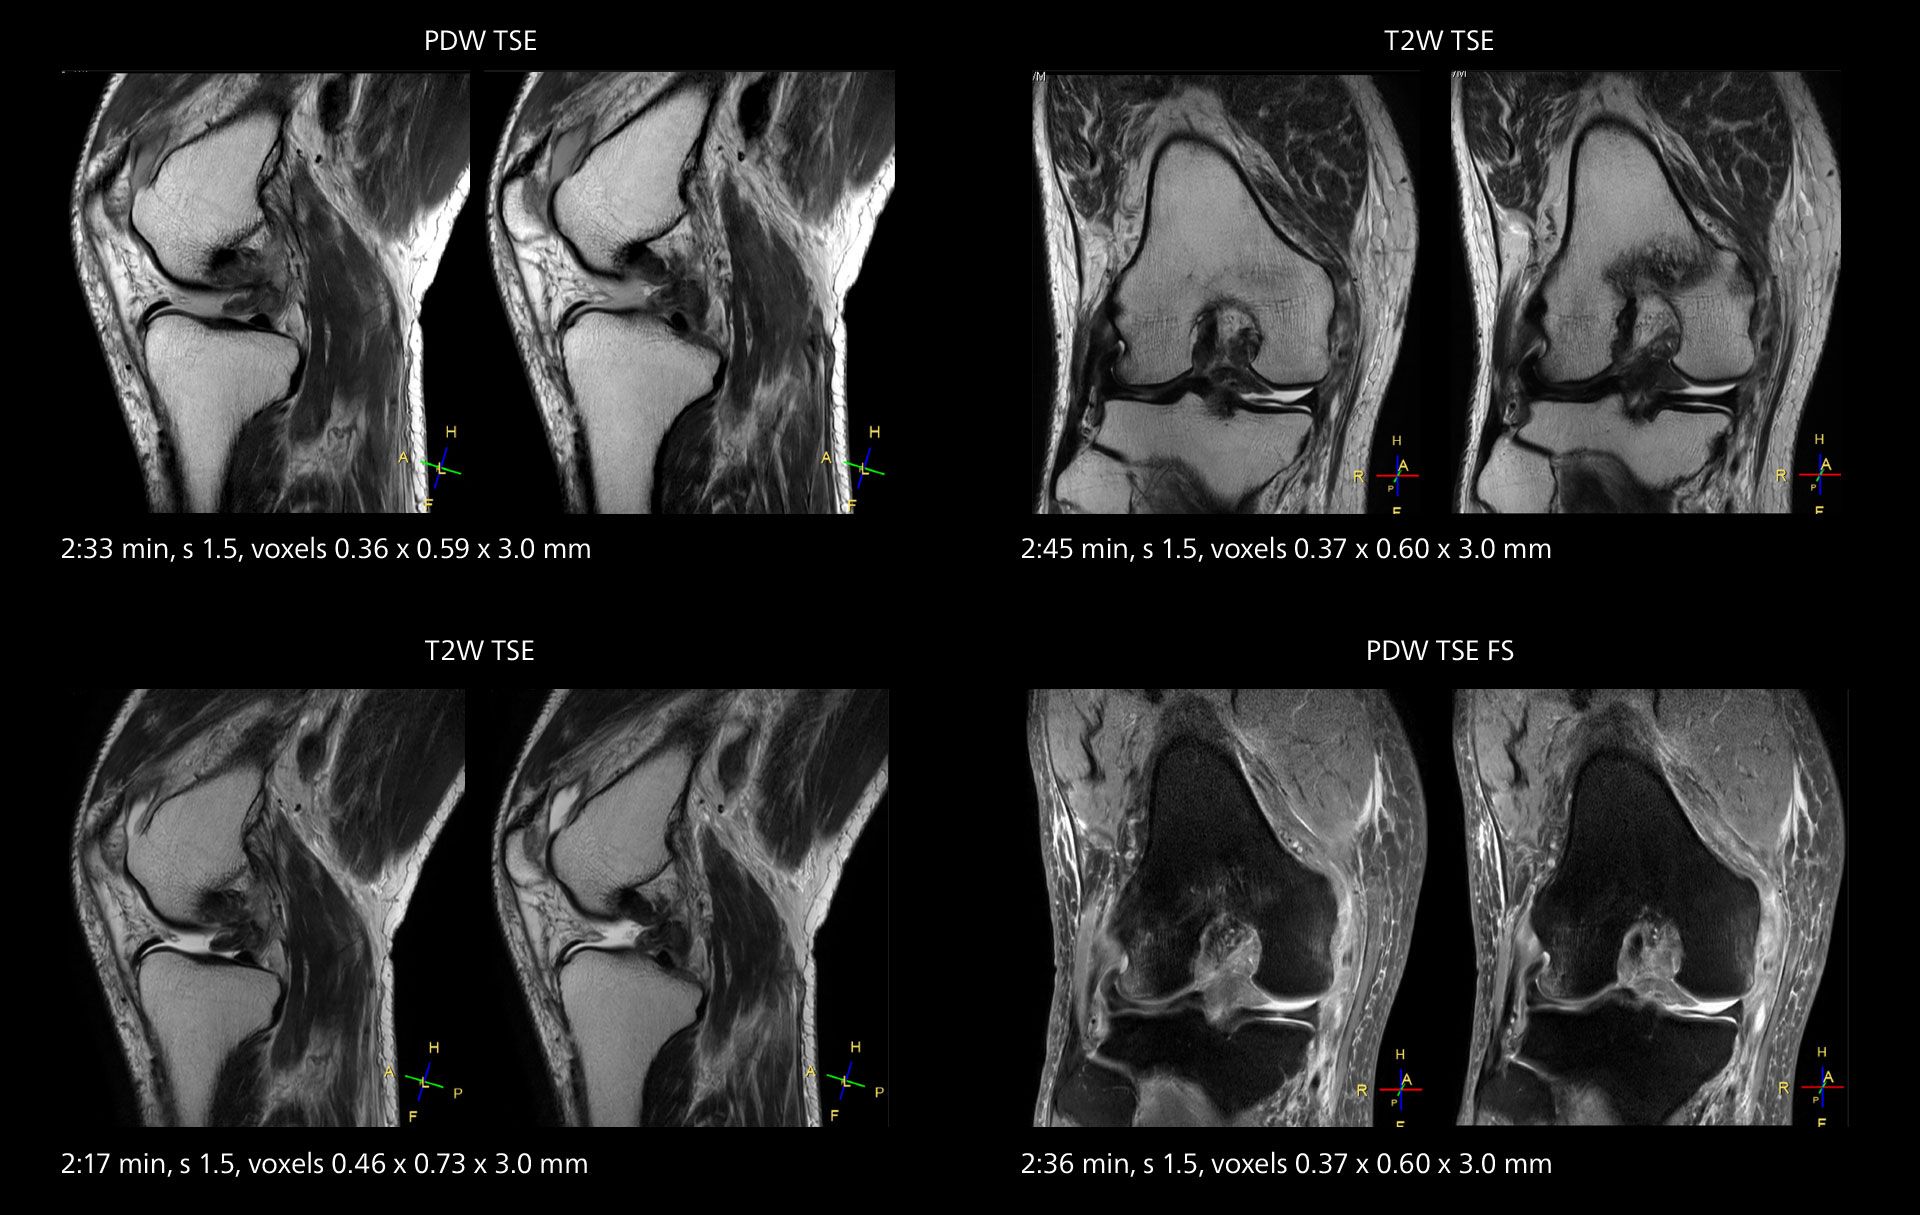

Images showing a posterior cruciate ligament (PCL) tear, a detached medial collateral ligament (MCL) on the tibial side and an intact anterior cruciate ligament (ACL). SmartPath to Elition X helped reduce scan time compared to previous imaging while maintaining resolution.

Overall, imaging time per sequence has been reduced since the Elition X upgrade. This can help reduce the risk of patient movement and the need for rescans. “As our hospital has many elderly patients, we consider it important to obtain high-quality data in a short time,” Dr. Makuuchi says. “Shorter imaging times are also useful for accepting emergency patients, because faster emergency studies have a reduced impact on the daily examinations schedule. In emergency cases it is also important that high quality images are obtained in a short time.”